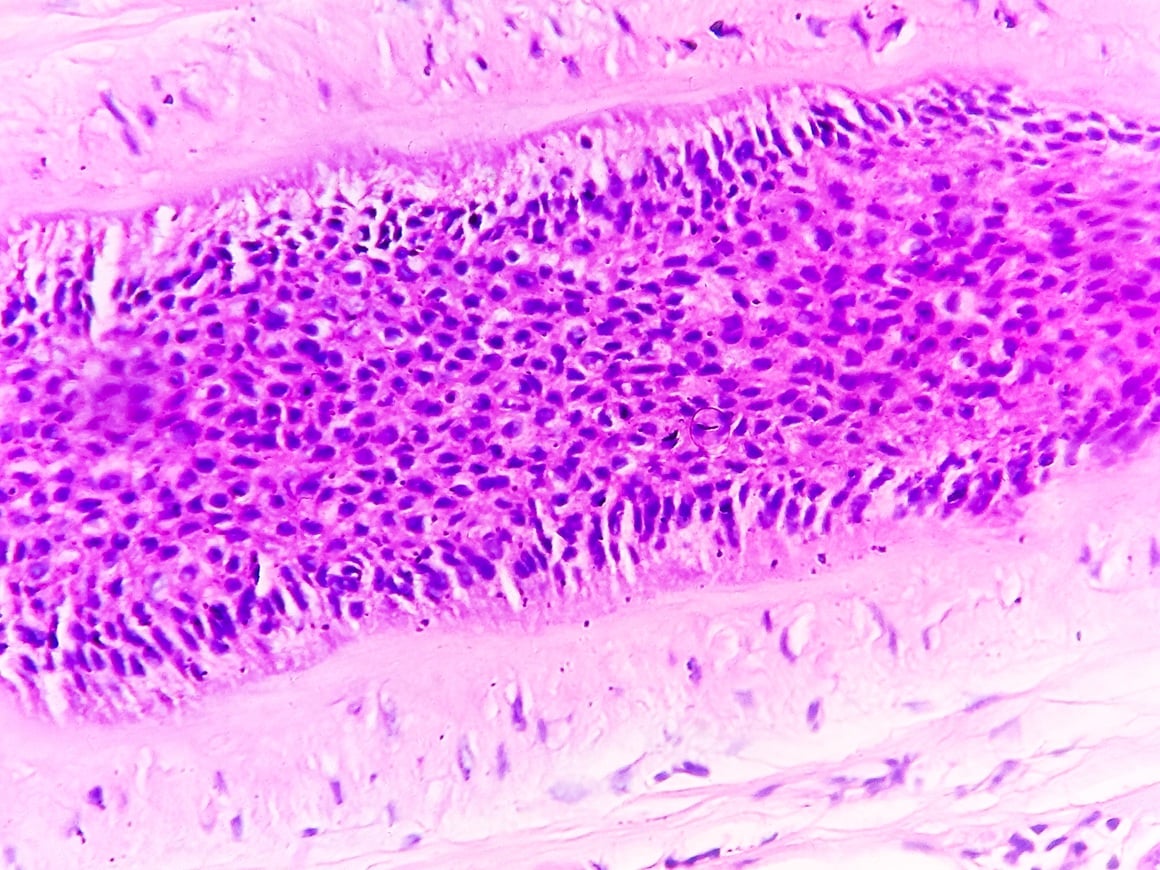

Kako izgleda karcinom in situ pod mikroskopom?

Dijagnoza se postavlja mikroskopskom analizom uzorka tkiva (biopsijom). Stanice kod kojih je potvrđen karcinom in situ pokazuju brojne abnormalnosti u usporedbi sa zdravim stanicama:

- promijenjen oblik i veličinu

- nepravilne jezgre

- ubrzano dijeljenje.

Iako izgledaju poput stanica invazivnog raka, ključna razlika je u tome što još nisu probile bazalnu membranu niti su zahvatile okolno potporno (stromalno) tkivo.